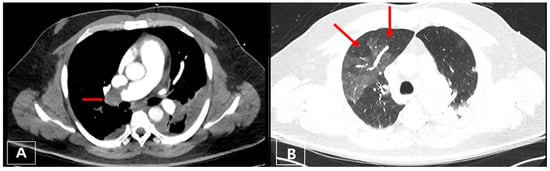

3.3. Imaging

3.4. Computed Tomography Pulmonary Angiography (CTPA)